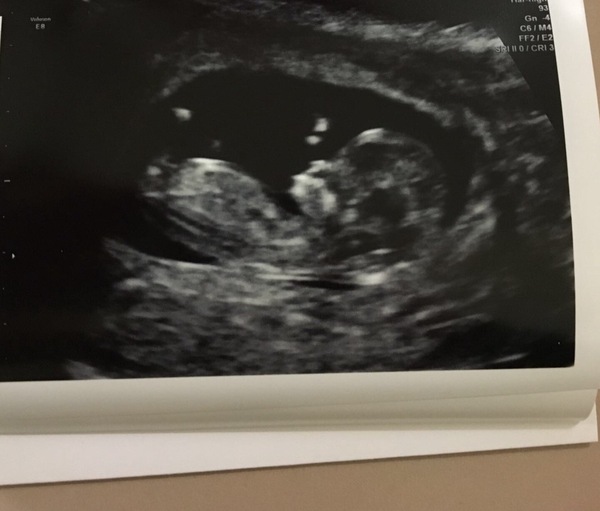

Scan all good. Measured just above 45mm but had to have sugary drinks and bounce about to get baby in the correct positon to do NT

Eek 11+2 today x

Dixie lovely scan picture.. it's so clear 😊😊

Dixie such a lovely scan!